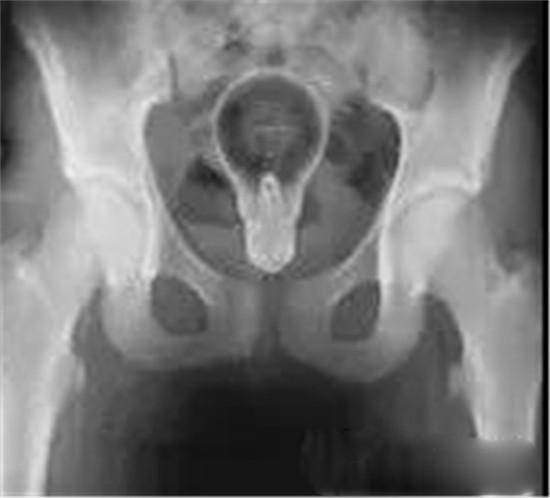

这是一个专门用于肛门自慰的性用品—肛塞。主人把它塞得太里面了。

透视下从肛门里夹取直肠里的东西

一般情况下,这些肛门异物的病人,来到医院后,医生都会给他上麻醉。把病人麻醉后,在透视下从肛门里夹取直肠里的东西。

一般情况下,用产钳可以取出大部分直肠异物。

如果从肛门里取不出,那就要开膛破肚了。